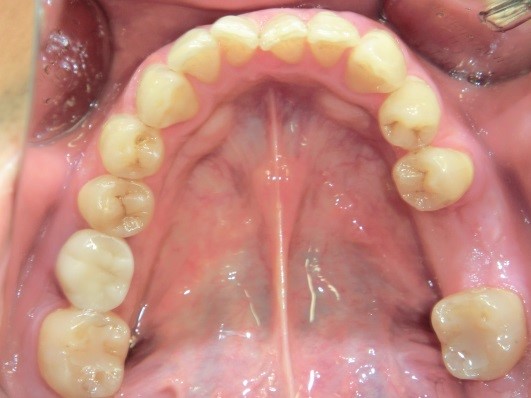

隣接する2本の歯をインプラントで治療した例

50代の患者様で、埋入したインプラントは2本、上部構造(人工歯)はジルコニアセラミックです。

こちらの患者様は、右下の第二小臼歯を第一小臼歯の2本を欠損されていました。写真の角度が異なっていますが、点線で囲んだ部分にインプラントを2本埋入して欠損治療を行っています。天然の歯とほとんど見分けがつきませんが、治療後の写真をよく見ていただくと、埋入したチタン製の土台(アバットメント)がわずかに黒っぽく透けているのにお気付きになると思います。普通に生活をされていれば、唇で隠れて全く気付かれない程度のものですが、より高い審美性を求められる方は、白いジルコニア製のインプラントもお選びいただけますので、ご相談ください。

下の奥歯にストローマンインプラント2本埋め込み、上部構造(人工歯)にジルコニアセラミックを選択した症例です。

| この症例の費用 | 約730,000円(税込・治療費込) |

|---|---|

| この症例の治療期間 | (約3回通院) |